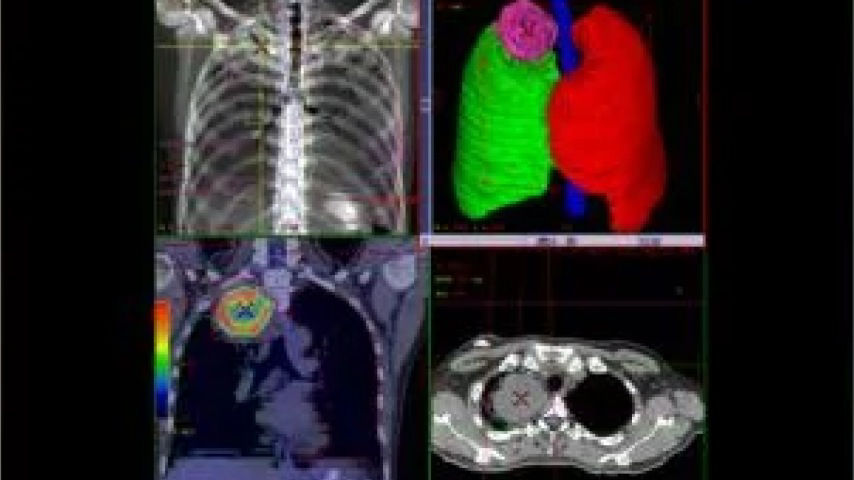

Multimodality Planning and Guidance

Now you can see some of the world's preferred guidance solutions all in one place. We believe in the power of precision health in the fight against cancer. After all, when you’re treating a disease on the cellular level, areas are defined by fractions of millimeters. As a result, you must have the right equipment and tools to precisely locate a lesion, diagnose it, define its shape, plan and guide its treatment, as well as monitor its progress.

Broad portfolio of solutions across precision imaging and radiopharmaceuticals enable radiation therapy planning and guidance with a focus on the individualized care pathway.